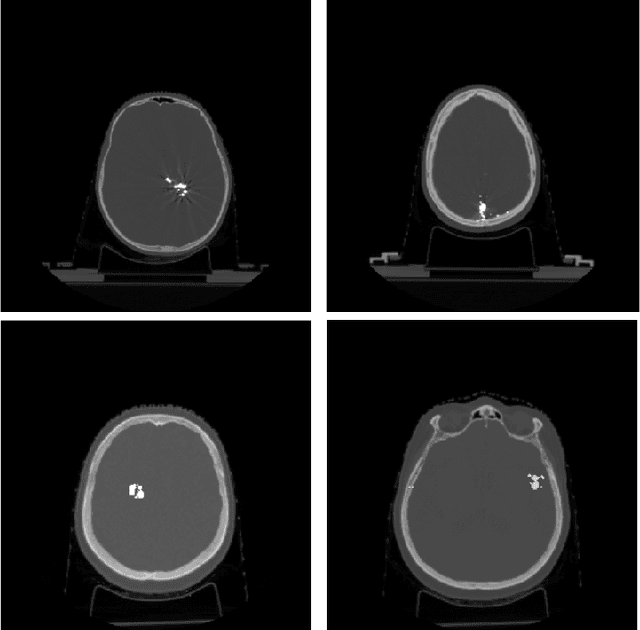

Abstract:Recent CT Metal Artifacts Reduction (MAR) methods are often based on image-to-image convolutional neural networks for adjustment of corrupted sinograms or images themselves. In this paper, we are exploring the capabilities of a multi-domain method which consists of both sinogram correction (projection domain step) and restored image correction (image-domain step). Moreover, we propose a formulation of the first step problem as sinogram inpainting which allows us to use methods of this specific field such as partial convolutions. The proposed method allows to achieve state-of-the-art (-75% MSE) improvement in comparison with a classic benchmark - Li-MAR.